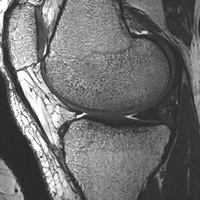

MR Image of the knee

MR image clearly defines anatomic

boundaries and bone structure.

Our computational models rely on the use of magnetic resonance (MR) imaging techniques, with special sequences and surface coils developed by our collaborators at the Rochester Center for Brain Imaging. With these techniques, we can capture not only the definition of the boundaries between tissues, but also information about the bone structure underlying the cartilage surfaces.

Our recent studies have shown that these images may be used to non-invasively predict bone mechanical properties with accuracy comparable to other more invasive techniques such as micro-computed tomography imaging. Possible future applications of this technique include clinical research for osteoporosis or osteoarthritis.